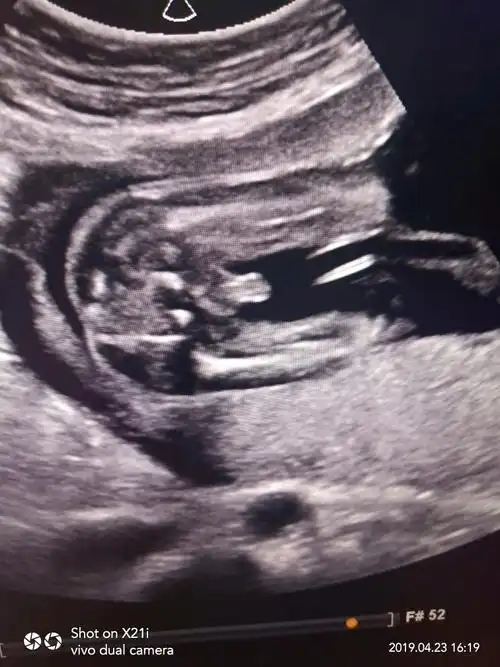

来来来,猜男女啦,生殖器附图